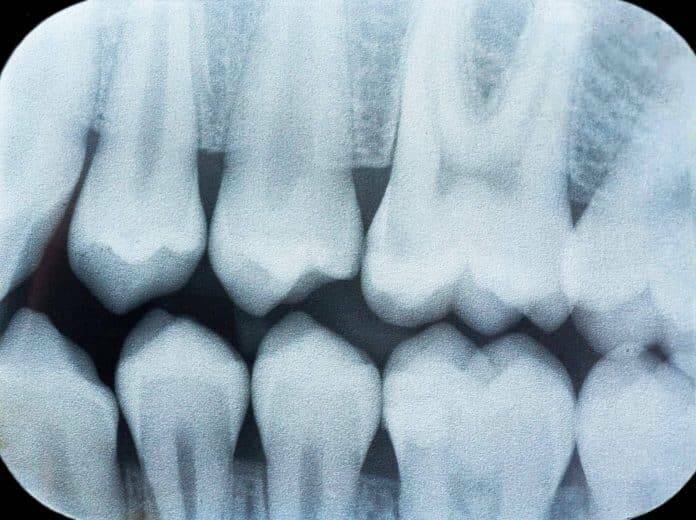

Con esta, se diagnostican distintas afecciones para diseñar los mejores tratamientos. Por ejemplo, logra identificar el grado de severidad en las caries, desde la estética hasta profundas infecciones en el nervio. En este último caso, el dentista programa una endodoncia en lugar del típico empaste.

Asimismo, evidencia el estado general del hueso, su cantidad y calidad, para llevar a cabo procedimientos de implantación dental específicos, de acuerdo con las necesidades del paciente.

Del mismo modo, la ortopantomografía muestra la estructura ósea, maxilar y mandíbula para analizar la mordida y los problemas de oclusión, con el objetivo de realizar ortodoncias de corrección en un tiempo determinado.

Además, la radiografía panorámica distingue las enfermedades periodontales como la gingivitis y la periodontitis. En general, si el cliente presenta bolsas o abscesos, también se establece la profundidad y el tamaño, para drenar, efectuar canal radicular o la extracción del diente.